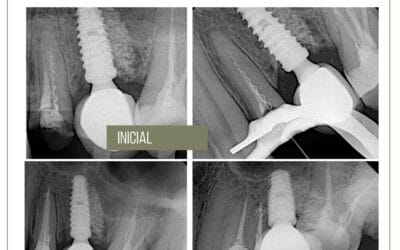

O retratamento do canal radicular é tradicionalmente considerado uma abordagem de tratamento “tudo ou nada”. É normalmente recomendado que todos os materiais restauradores e de obturação devem ser removido de todas as raízes, independentemente da presença ou ausência de patologia periapical. Ao contrário, a cirurgia a endodontia não é vista como um tratamento com abordagem “tudo ou nada”, Tradicionalmente, apenas a(s) raiz(es) doente(s) é(são) abordada(s) por meio de ressecção apical e obturação apical.

O uso da tomografia computadorizada de feixe cônico permite uma avaliação mais precisa da condição periapical de raízes individuais. Esta informação introduziu uma nova e conservadora alternativa de tratamento para dentes previamente tratados endodonticamente com múltiplas raízes apresentando doença pós-tratamento. Esta nova abordagem é denominada retratamento radicular seletivo. Imagem avançada permite ao clínico tomar decisões de tratamento previsíveis com relação à presença ou ausência de patologia periapical de raízes individuais, em vez de tomar suposições sobre o dente como um todo. Seletivo retratamento radicular combina a abordagem de tratamento não cirúrgico retratamento com a seletividade da ressecção cirúrgica da raiz. Desta forma, o retratamento pode ser limitado a uma única raiz ou raízes mostrando claramente a patologia periapical enquanto deixa a(s) raiz(es) sem nenhum sinal visível ou percebido patose intocada.